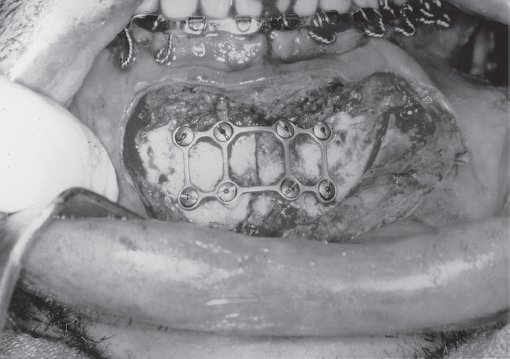

With the ideal plate position identified, the osteosynthesis line overlying the inferior alveolar nerve and tooth roots remains a problem. The solution is the monocortical screw. A monocortical screw penetrates only the lateral cortex of the mandible, and great care is exercised to avoid deeper penetration into the alveolar nerve and tooth roots. When performing these procedures, the surgeon must be aware of the location of the tooth roots and of the inferior alveolar nerves. It should also be clear that the use of monocortical screws precludes the application of compression because compression plating puts pressure on the screw shaft at its entry point into the bone; the thin monocortical fixation of the screw to the bone will likely be inadequate to prevent shifting of the screw, which would lead to loosening and failure. Nonetheless, the plates and screws used must be strong enough to resist the distracting forces that occur in function. Two-millimeter mandibular miniplates are designed to overcome these forces, and, when properly applied, fixation failure is uncommon. However, many failures have resulted from the use of inadequate fixation, as may be seen when weaker plates designed for midfacial applications are applied to the mandible. The facial plastic surgeon must be familiar with the systems and must be sure to select implants designed for the particular indications for which they are being used. Similarly, the screws must be of appropriate size, strength, and number, and they must hold tightly in the bone. If a screw hole strips during screw tightening, it must be abandoned, as it will not provide fixation. A larger (“emergency”) screw may be utilized or the plate must be moved and new holes used. A variation of the miniplate technique is the use of the “threedimensional plate” applied along the line of tension as described by Farmand. 9 The threedimensional plate is actually a miniplate that has been strengthened by being produced in geometric assemblies of squares and rectangles ( Fig. 61.5 ). Although the plates are slightly more difficult to bend, the results using them have been excellent.